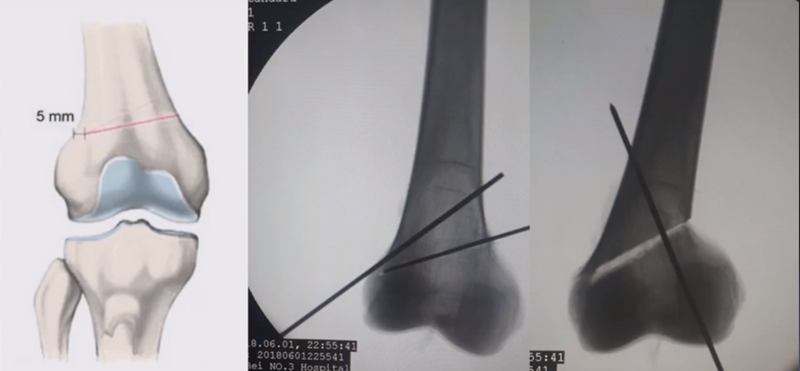

合页点的选择与HTO一样,通常需要尽可能接近畸形部位,既要有很好的骨质结构,还要有坚韧的软组织覆盖,以保证稳定性和术后有良好的血运。合页宽度不宜太长,通常保留在5mm。

注意,目前临床推荐的DFO要求最好能做双平面截骨,即还要有一条上行截骨线,上行截骨线与水平截骨线夹角大概为95° 左右。这种截骨方式一方面可以增加稳定性,同时也可以减少对上方髌股关节的干扰。

上行截骨时,要保持肢体旋转中立位,前方要有骨撬保护,由内向外完全截开,上行截骨线不存在合页。

水平截骨时,同样放肢体中立位,后侧放一把骨撬保护后方重要结构。

截骨过程中,不要求一次截骨到位,把合页深度全部截到,可以留最后一点,用钻头由前向后打出一排筛孔来,把合页端弱化,再去做闭合时就不容易折断了。